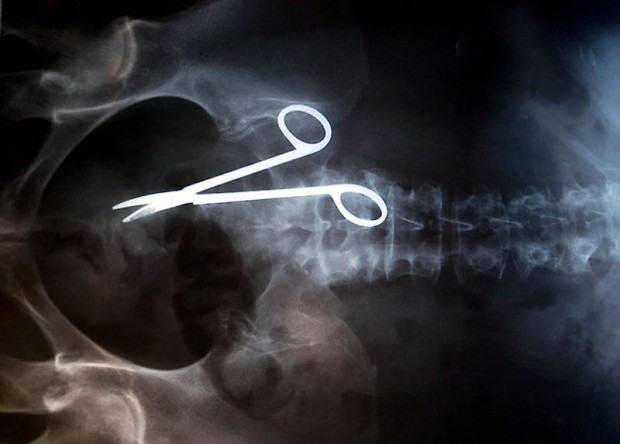

12. Хирургические ножницы, случайно забытые в теле пациентки после операции. Ножницы были обнаружены лишь через 18 месяцев после операции, т.к. женщина жаловалась на постоянную боль в кишечнике.